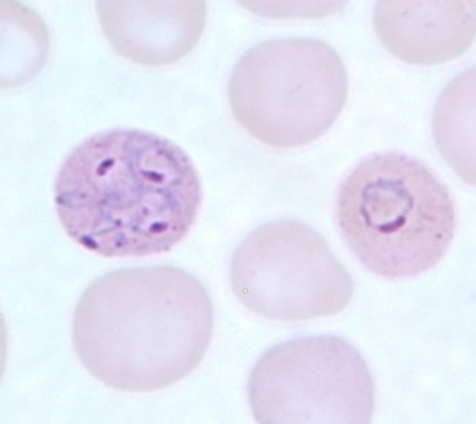

Plasmodium malariae

Plasmodium malariae